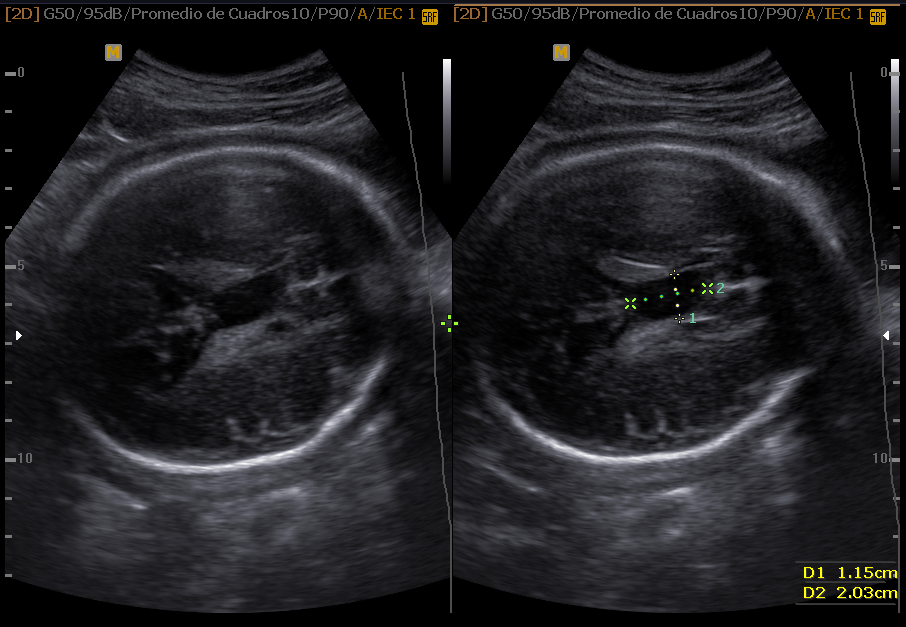

Las estructuras intracraneales después de la semana 18-20 del embarazo son muy características y permanecen visualmente invariables hasta el final del embarazo, solo modificando sus tamaños a medida que el feto crece. Esto es de gran ayuda ya que permite determinar la aparición de cambios que podrían sugerir desviación de la normalidad y aparición de una malformación congénita o lesión adquirida por eventos externos especialmente relacionados a infecciones y accidentes vasculares fetales.

Cuerpo calloso: es una estructura compuesta por haces nerviosos cuya función es la de conectar e integrar regiones corticales homólogas entre ambos hemisferios cerebrales. Su ausencia total puede conducir a problemas cognitivos y del desorrollo psicomotriz o pasar totalmente desapercibida. Su ausencia parcial, paradójicamente, se asocia con peor pronóstico. Como estructura ecográfica, es una de las más bellas que hay en el cerebro pero, para obtenerla se requiere pericia y muy buena resolución ecográfica. Sus alteraciones congénitas son diagnóstico de problemas primarios del desarrollo cerebral y se manifiestan con cambios indirectos en otras secciones cerebrales, especialmente ventriculomegalia.

En este resúmen gráfico se incluye la mayor parte de las lesiones cerebrales congénitas visibles en vida fetal; los cortes transversales expuestos aquí son insuficientes para algunas de ellas y los hallazgos pueden modificarse en el tiempo, usualmente manifestando mayor número de elementos anómalos. Muy pocas condiciones mejoran con el tiempo